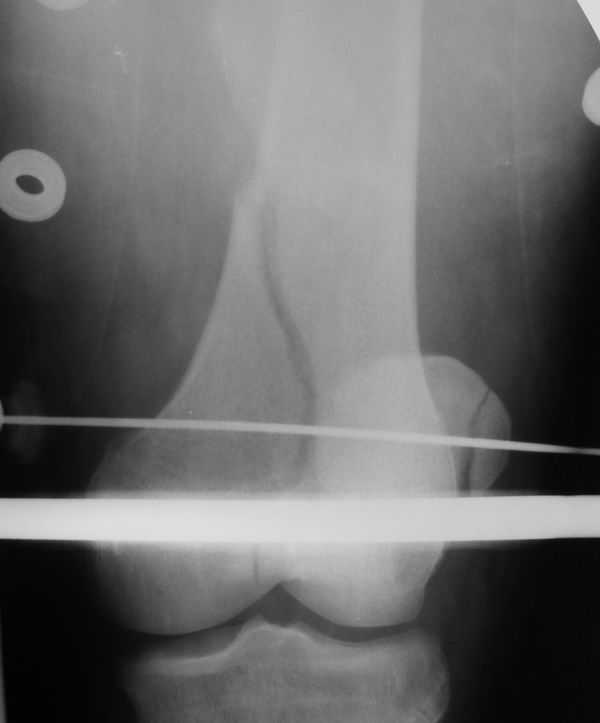

Лечился в ЦРБ. К нам поступил вчера. Имеется оскольчатый перелом диафиза левого бедра, перелом медиального мыщелка, краевой перелом надколенника. У нас, кроме того, выявили перелом шейки бедра. Перелом закрытый, имеется рана в в/3 голени(ниже уровня бугристости б/берцовой кости)без признаков инфицирования.Планируем закрыто фиксировать мыщелок и надколенник винтами, затем закрыто заштифтовать бедро. Вопрос возник по перелому шейки: что предпочесть - длинный PFN или DFN + DHS на шейку?Буду благодарен за ценные советы.С уважением, Станислав Дмитриев.

Заранее приношу извинения за качество снимков. То что есть - либо из ЦРБ, либо сделано в приемном покое, где дежурят рентгенлаборанты различной квалификации. Завтра постараемся сделать снимки всего бедра на длинные кассеты в 2 проекциях. Сейчас больной на скелетном вытяжении. Состояние стабильное.

Я тоже склоняюсь к такой версии.Перелом практически базальный, тип Пауэлс 3 - однозначно нужна угловая стабильность - ни о каких спонгиозных винтах речи нет. Возраст 46 лет, т.е. достаточно молодой - насчет ас. некроза. Накладку DHS вероятно придется ставить монокортикально - штифт получается до малого вертела. Померили расположение имплантов - что называется "стык в стык".